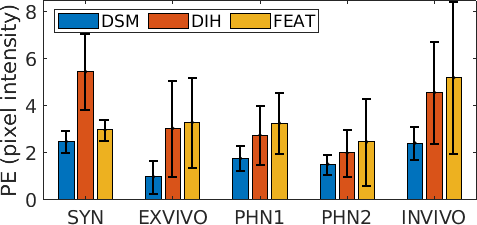

For experimental analysis, we use 5 fetoscopic videos (Table. 1), which include a synthetic video (SYN) - a discontinuous version of this sequence was used in [11], an ex-vivo in water (EX) data reported in [5], a placenta phantom (PHN1), a TTTS phantom111TTTS phantom from Surgical Touch Simulator: https://www.surgicaltouch.com/ in water (PHN2) depicting an in-vivo procedure and an in-vivo TTTS procedure (INVI). Note from Table. 1 the variability in visual quality, appearance, resolution, imaging source, camera views and captured motion. These variations pose challenging scenarios for mosaicking methods.

The visualization and comparison results on one circular loop (360 frames) of the SYN sequence are shown in Fig. 3(a)-(c). Note the small drift in DSM compared to FEAT. Similar behavior is observed from the mean residual error in Fig. 3(d) where the errors are reported for FEAT, DIH and DSM for the complete length of the sequence (811 frames). It can be seen that the error for FEAT starts increasing after approximately 300 frames and the mosaic starts drifting away. DIH error explodes within a few frames due to the random perturbation during training (Sec. 2). On the other hand, the error for DSM is very small and remains bounded. This is further verified from the low RMSE (0.36) and photometric (2.48) errors for DSM (Fig. 4). Comparison of our proposed DSM with FEAT and DIH is presented in Fig. 4. Overall the pairwise homography errors are high for FEAT for all five sequences due to poor visual quality and lack of texture in the fetoscopic videos. The RMSE and photometric errors for DIH are low compared to FEAT but are always higher compared to DSM (e.g. RMSE on EX for DIH (1.64) and DSM (0.38)). In DIH, this error accumulated over time during mosaic generation and resulted in a large drift. For EX, PHN1, PHN2 and INVI sequences, the average RMSE errors are 0.38, 0.32, 0.35 and 0.34, and photometric errors are 0.98, 1.76, 1.52, 2.42, respectively.

Mosaics generated using the proposed DSM for the EX, PHN1, PHN2 and INVI sequences are shown in Fig. 5. These mosaics are best assessed in the supplemental video that shows the qualitative comparison with respect to FEAT and DIH. DSM created a meaningful mosaic for EX (unseen data) with minimum drift accumulation over time which can be observed from the start and end frames in Fig. 5(a). PHN1 contained non-planar views without occlusions with a freehand circular trajectory. DSM generated reliable mosaics with minimum drift (Fig. 5(b)), however FEAT drifted away due to non-planar views, insufficient feature matches and long-range videos. PHN2 and INVI represent the most challenging scenarios containing highly non-planar views with heavy occlusions, low resolution and texture paucity. We observe from Fig. 5(c)(d) that although the generated mosaics can serve well for increasing the FoV, yet there is a noticeable drift due to highly challenging conditions. Such errors may be corrected by end-to-end training using the photometric loss [8].